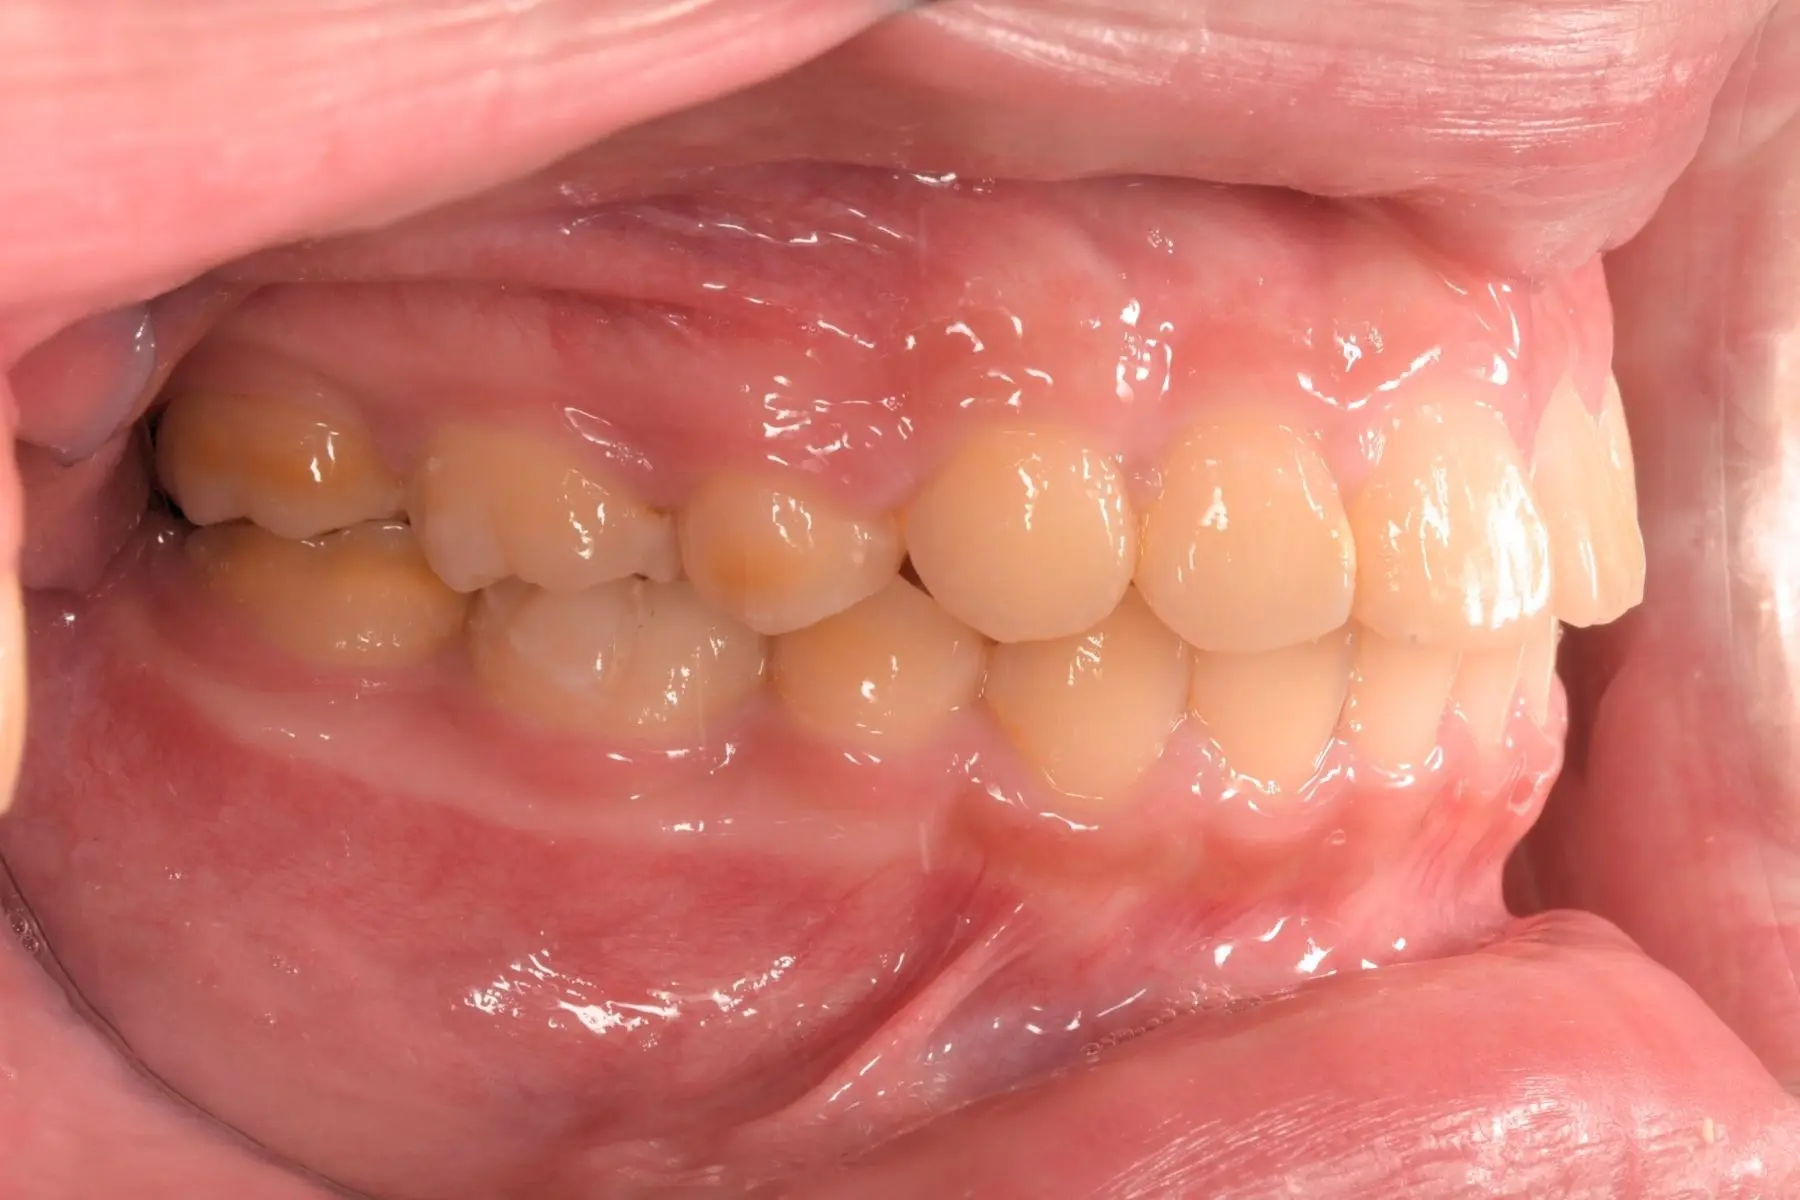

術前術後對比

自鎖式矯正_術前

自鎖式矯正_術後